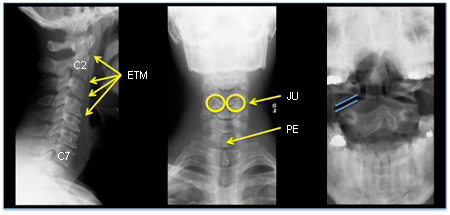

Coluna cervical normal: incidências lateral, anteroposterior (AP), e odontoide com boca aberta

Do acervo pessoal de Michael G. Fehlings